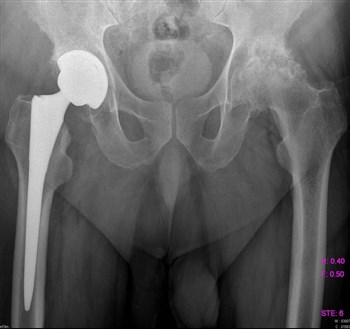

Артроз тазобедренного сустава

Все чаще и чаще пациенты обращаются с жалобами на боли в паху, в колене, иногда на боль в ноге, на скованность движений, нарушение походки.

Как правило, страдают таким недугом женщины после 40 лет.

Боль локализуется в вышеуказанных местах как на одной, так и на обеих ногах.

Проведенная диагностика покажет, в какой стадии находится заболевание, будет дана точная информация о состоянии мягких и костных тканей.

Если заболевание не в хронической форме, или, проще говоря, не запущено, то лечение происходит обычным парацетамолом, без какого-либо хирургического вмешательства. Лечащий доктор назначает курс массажа, лечебной гимнастики, постоянный контроль ортопеда. При ноющих болях прописывается курс болеутоляющих – Кеторол, Диклофенак.

Асептический некроз головки бедра

Все симптомы примерно те же, что и при других заболеваниях, связанных с суставами. Все же важным отличием является постоянная неутихающая боль в бедре, атрофия мышц, укорочение конечности, хромота.

Асептическому некрозу головки бедра подвержены мужчины, особенно после травм – перелома, вывиха или хирургического вмешательства, так как повреждаются сосуды, кровь проходит хуже и они закупориваются тромбами.

В зависимости от запущенности болезни, проводят медикаментозное или хирургическое лечение.

Медикаментозное лечение проводится в том случае, если нет признаков разрушения кости и уровень кальция в организме в пределах нормы.

Хирургическое вмешательство показано при острой форме заболевания или если медикаментозная терапия не дала положительных результатов.